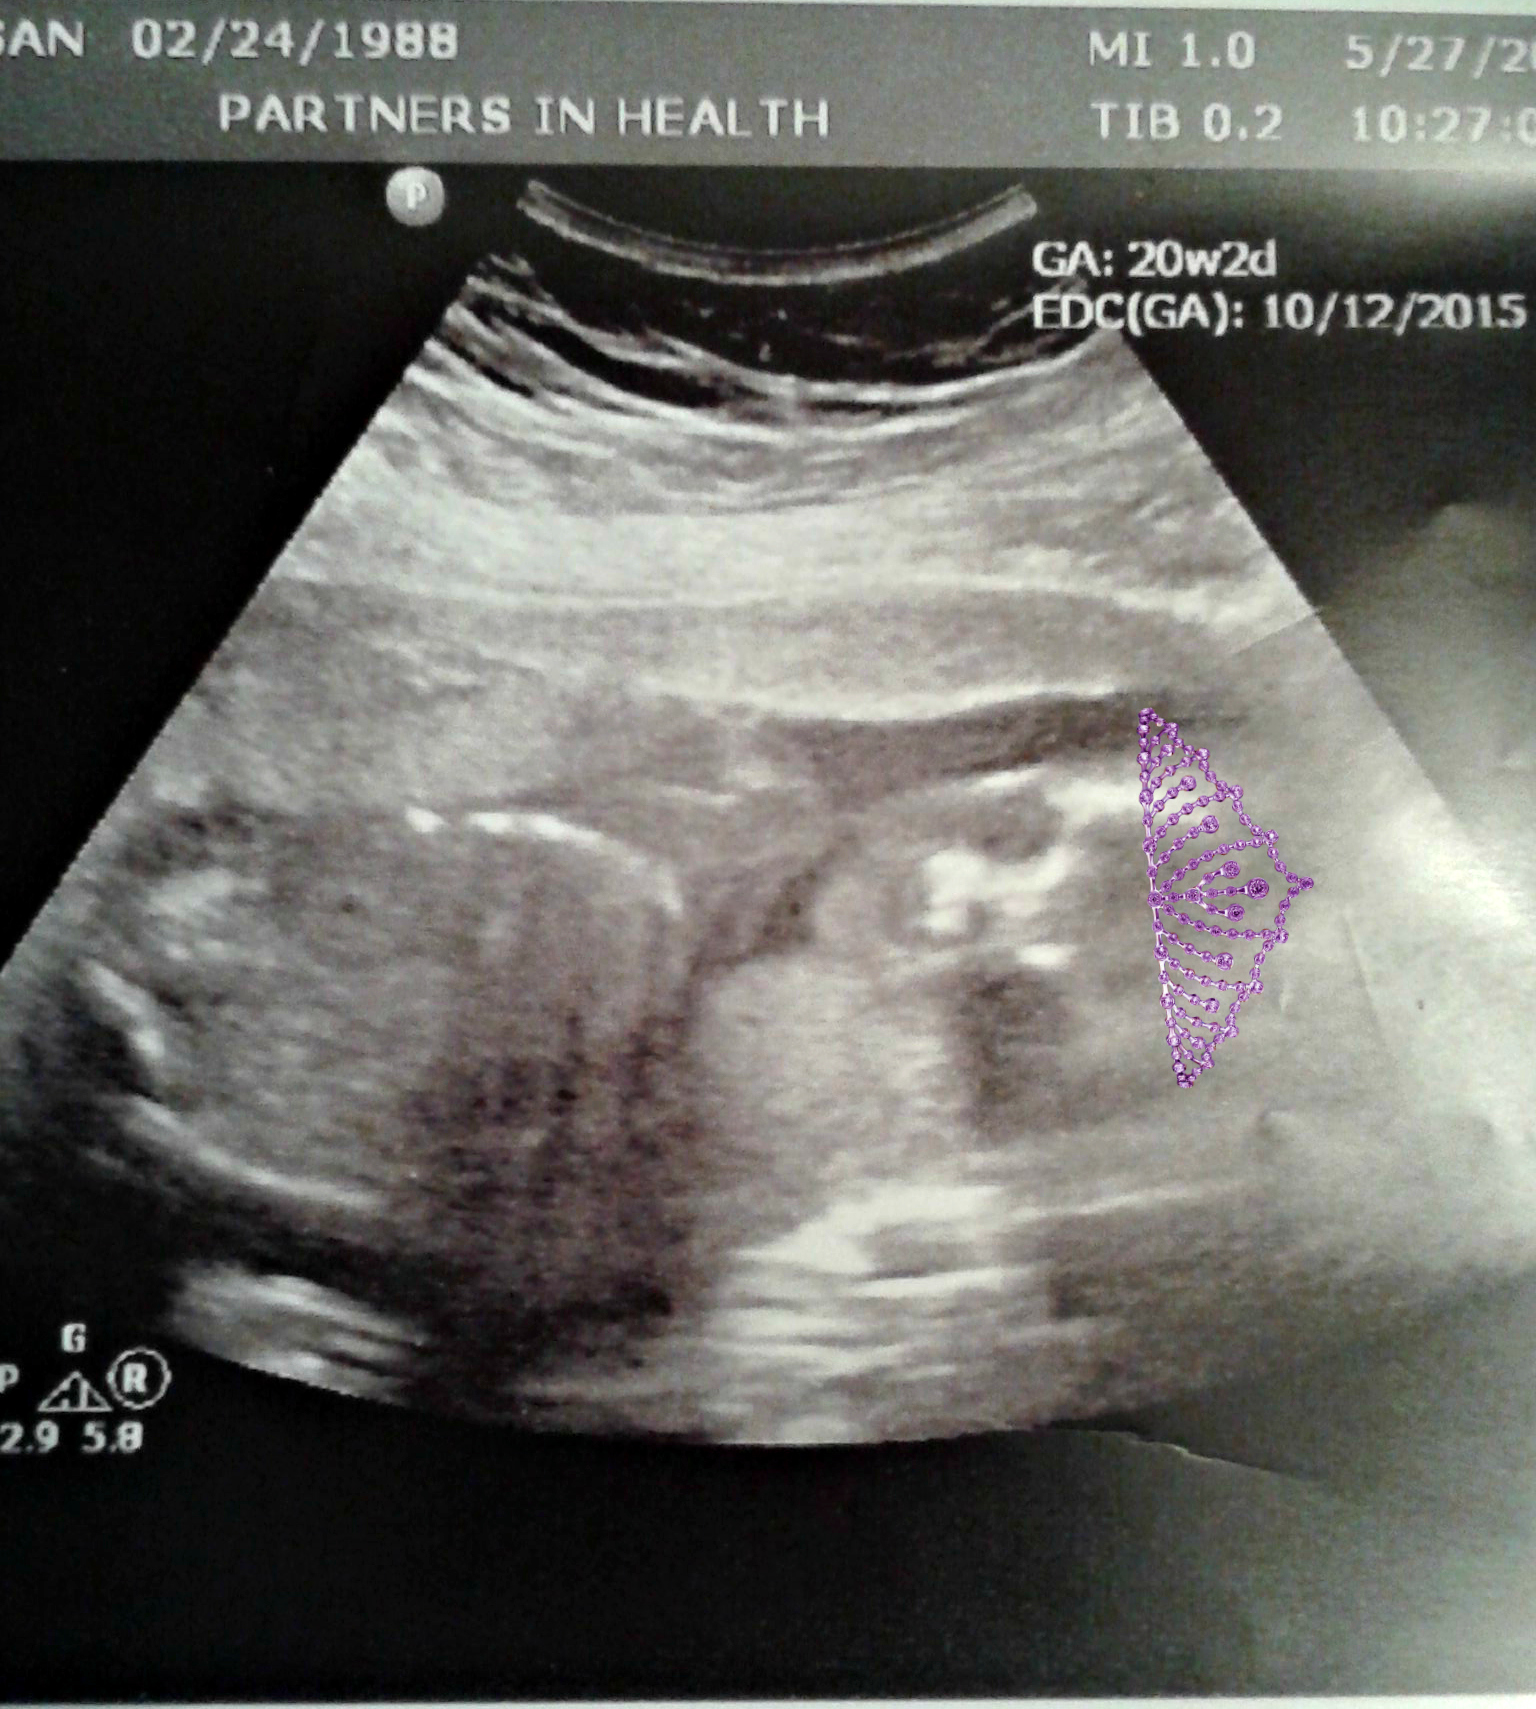

#TeamPink.